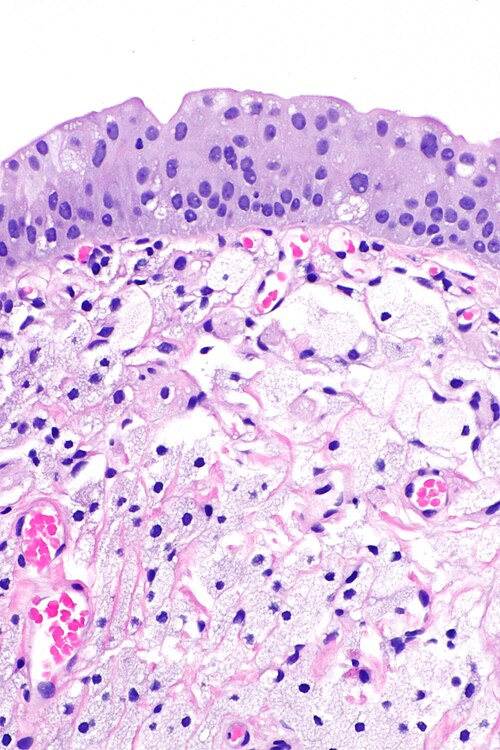

Intermediate magnification

Intermediate magnification. H&E stain.